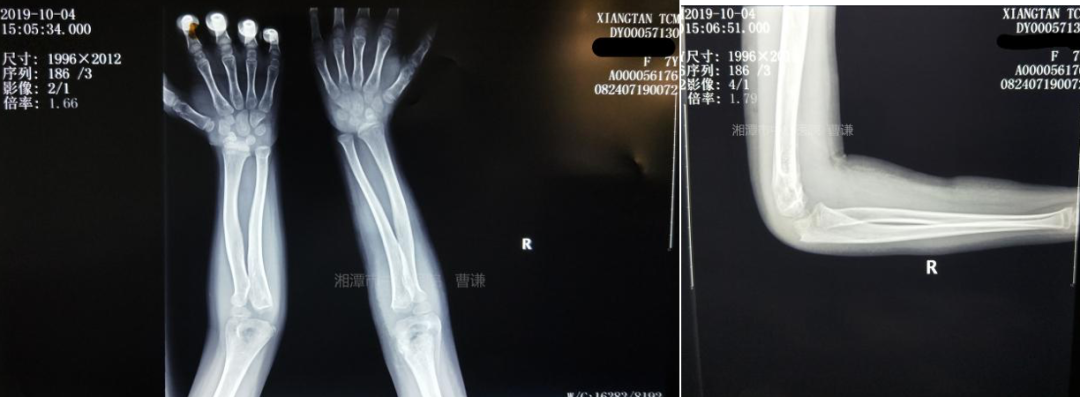

拍片复查骨折对位对线可。

伤后一月余拍片复查见骨折对位对线良好,骨痂生长明显。

伤后三个月随访拍片复查见骨折愈合良好。